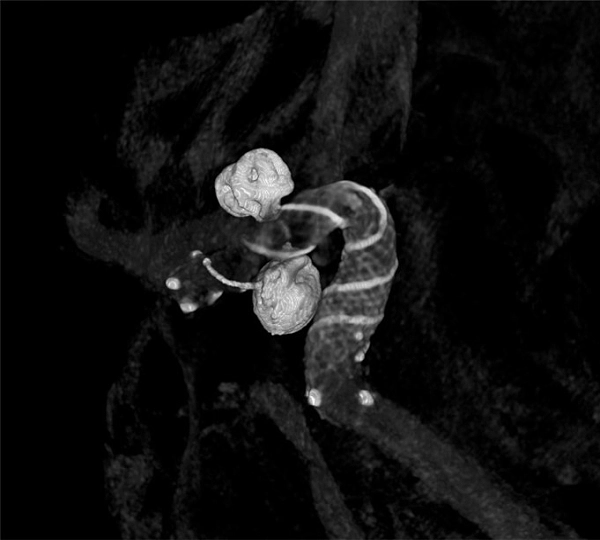

Čtyři mozkové výdutě před ošetřením. Foto: Krajská zdravotní

Céva po výkonu. Foto: Krajská zdravotní